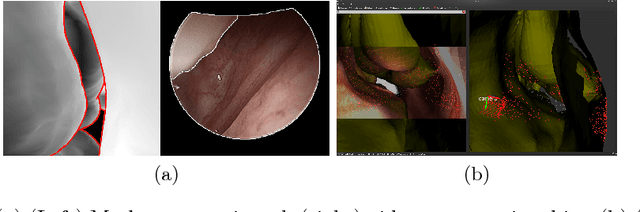

Abstract:Clinical examinations that involve endoscopic exploration of the nasal cavity and sinuses often do not have a reference image to provide structural context to the clinician. In this paper, we present a system for navigation during clinical endoscopic exploration in the absence of computed tomography (CT) scans by making use of shape statistics from past CT scans. Using a deformable registration algorithm along with dense reconstructions from video, we show that we are able to achieve submillimeter registrations in in-vivo clinical data and are able to assign confidence to these registrations using confidence criteria established using simulated data.

Abstract:Functional endoscopic sinus surgery (FESS) is a surgical procedure used to treat acute cases of sinusitis and other sinus diseases. FESS is fast becoming the preferred choice of treatment due to its minimally invasive nature. However, due to the limited field of view of the endoscope, surgeons rely on navigation systems to guide them within the nasal cavity. State of the art navigation systems report registration accuracy of over 1mm, which is large compared to the size of the nasal airways. We present an anatomically constrained video-CT registration algorithm that incorporates multiple video features. Our algorithm is robust in the presence of outliers. We also test our algorithm on simulated and in-vivo data, and test its accuracy against degrading initializations.